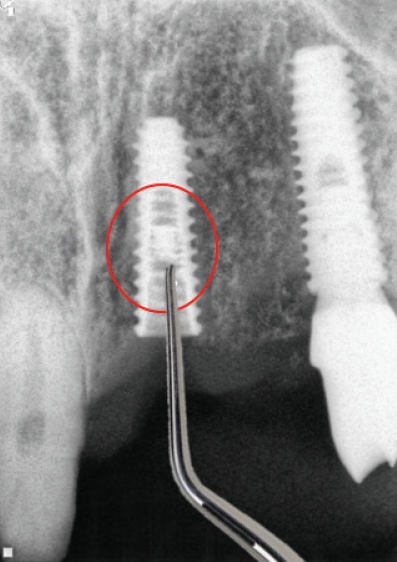

2005년까지는 국민건강보험요양급여의기준에 관한 규칙에서 치아의 보철치료(보철재료 및 기공료등 포함)는 비급여대상으로하고 있으며 보철의 범주에 속하는 임프란트 또한 비급여 대상으로, 임프란트시술 후 이와 직접 연관된 합병증 및 후유증 치료는 비급여토록 하였다. 2005년 5월 11일 진료평가심의위원회는 임프란트 치료시 최종철물을 장착하고 6개월이 경과한 후 발생한 임프란트 주위염, 임프란트 동요 및 파절 등은 이와 직접적인 진료로 보기 곤란하므로 요양급여로 인정키로 함으로서 한동안은 임프란트 주위염, 임프란트 동요 및 파절(Fig. 1) 등 3가지 경우에 한하여 기존의 건강보함항목을 적용받을 수 있는 근거가 마련되었다.

따라서 이 시기에는 임플란트를술에 대하여, 간단하게 포셉으로 제거하는 경우에는 전치단순발치술 또는 구치단순발치술 등 식립된 임플란트의 위치에 따라 보험항목을 적용하였으며 버(bur)등으로 골삭제를 하면서 제거하는 경우에는 난발치 항목을 적용하고 버값(6,980원)을 청구하는 방식을 임상에서 사용하였다. 이후 2014년 7월 1일 임플란트 관련 항목(제거술, 치과건강보험적용기준)들이 신설되고(Table 1) [4], 후유증 인정기준에 대한 심사지침이 변경되었다(Table 2).

임플란트는 많이 심을수록 확률적으로 실패도 늘어나고 이에 따라 임플란트를 제거해야 하는 경우도 늘어나게 되었다. 2014년 7월 1일 임플란트 제거와 관련된 고시가 새로 발표된 이후로는 단순과 복잡으로 정리되었다. 단순 임플란트제거술은 임플란트 동요도가 있는 경우로 정의되어 구강내 식립 위치에 무관하게 적용되고 있다. 반면에 복잡 임프란트제거술은 동요도가 없는 경우에 임플란트 주위염, 파절 신경손상 등에 적용되는데 trephine bur 또는 별도의 제거 전용 키트를 사용하는 경우에 적용된다. 따라서 버를 사용하지 않더라도 라쳇(rachet)이나 토커렌치(torque rench) 등으로 제거하는 경우에도 적용 가능하다.

주의해야 하는 사항은 trephine bur를 사용하고서는 별도의 비용을 추가로 청구하는 것은 허용되지 않는다는 것이다(Fig. 2), trephine bur를 처음 사용하는 경우 주의해야 하는 것은 적용 시에 역회전으로 방향을 먼저 잡은 이후 정방향으로 바꿔서 제거해야 한다는 것이다. 임플란트 보다 사이즈가 큰 것을 사용해야 하는데 시판되는 trephine bur는 내경과 외경이 보통 1mm의 차이를 보인다. 따라서 4mm 직경의 임플란트를 제거하기 위해서는 내경이 4mm 이상 이어야 히고 외경은 5mm 이상이 된다 그러나 현실적으로는 내경이 5mm이상인 것을 적용해야 제거가 쉬우므로 제거 후 결손부가 굉장히 광대하게 발생 된다.